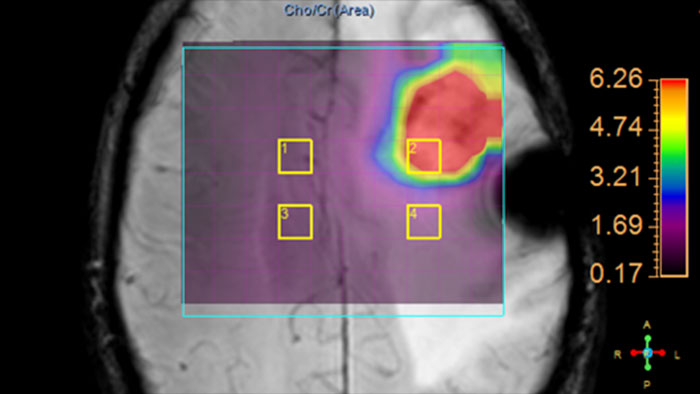

Review metabolite maps

MR SpectroView is a task-guided application providing hydrogen single voxel spectra as well as metabolic and ratio maps. It automatically identifies the anatomy to preselect appropriate metabolites or supports user-defined combination of metabolites.

Benefits